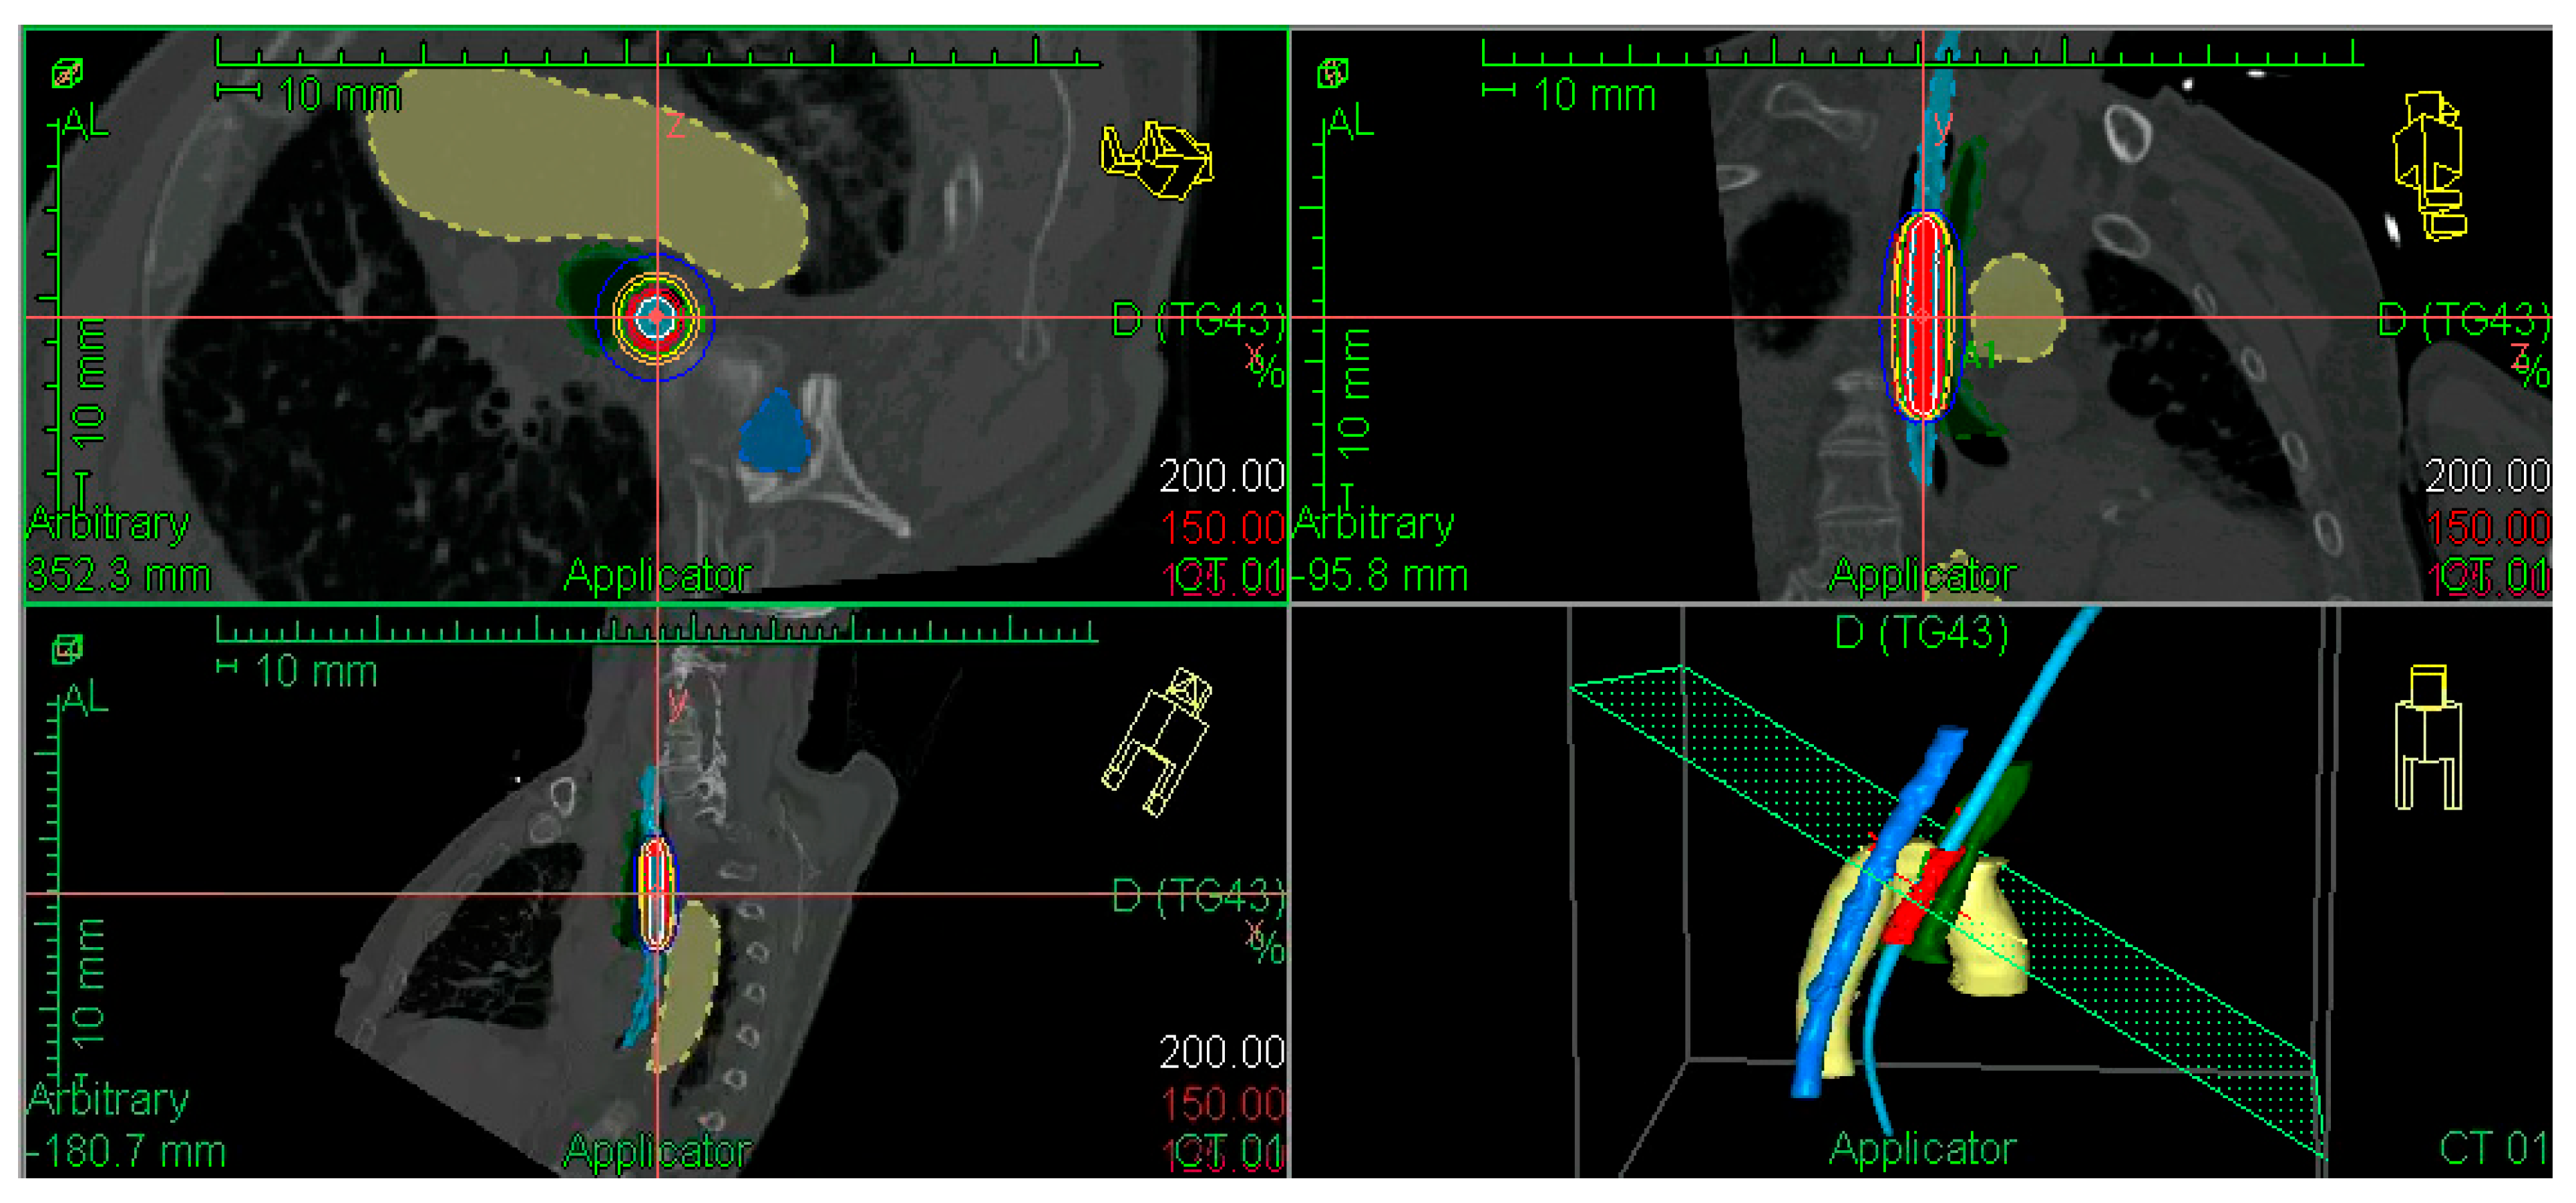

2.2. Brachytherapy Treatment